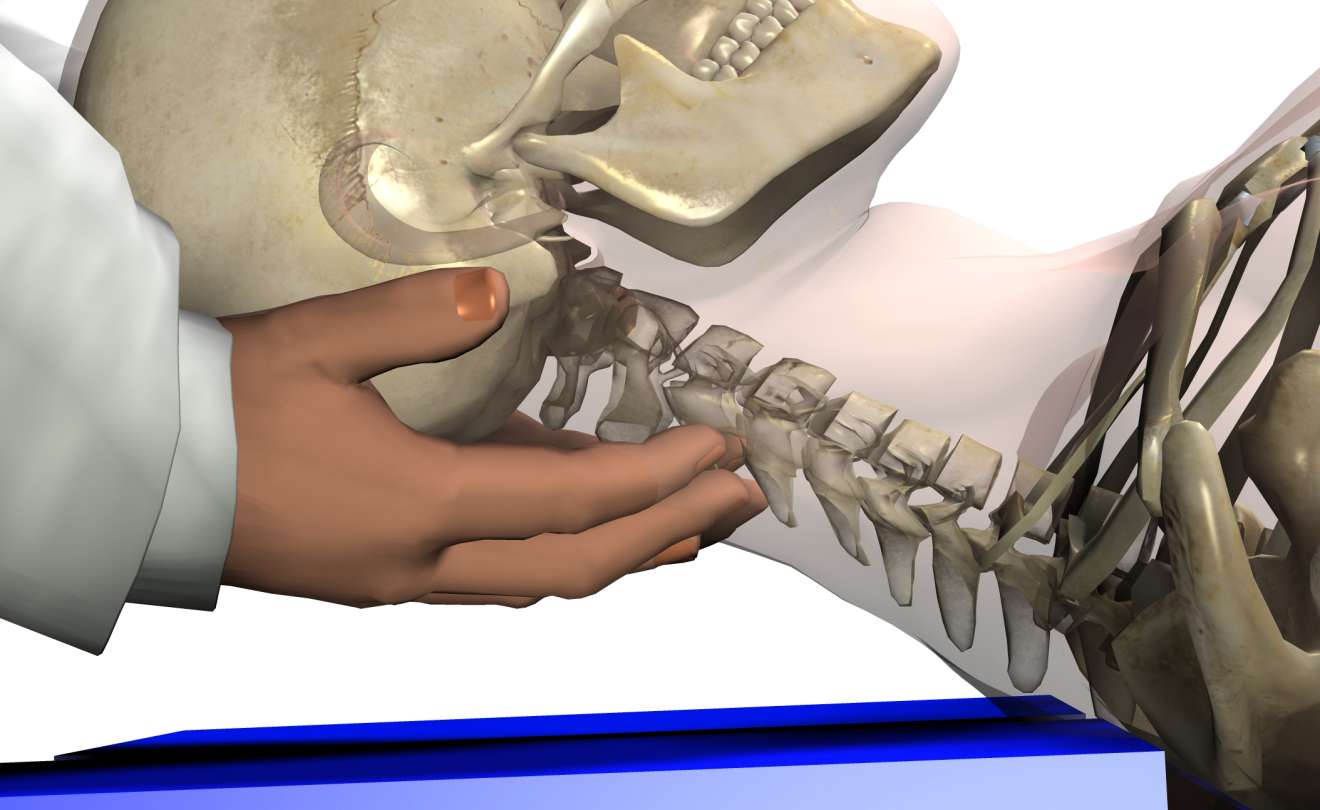

絶対的な信頼 クリニカルカイロプラクティック: 特定的なバイオメカニカル 健康・医学

絶対的な信頼 クリニカルカイロプラクティック: 特定的なバイオメカニカル 健康・医学

クリニカルカイロプラクティック: 特定的なバイオメカニカル,

クリニカルカイロプラクティック: 特定的なバイオメカニカル, バイオメカニカルアプローチ セミナー 2025|PT-OT-ST.NET,

Amazon | ABUZIV 6H5-85570-00 61N-85570-00-00 61A-85570-00-00, バイオメカニカルアプローチ セミナー 2025|PT-OT-ST.NET「クリニカルカイロプラクティック 特定的なバイオメカニカルアプローチ」栗原 輝久 / 前田 滋 / 小柳 公譽定価: ¥ 18000カイロプラクティック学習時使用しました。【未使用】解剖学。本に蛍光ペンによるライン引きや学習メモなどされています。標準組織学総論。中古本と言うことをご理解の上ご購入ください。完全写真図解 初夜新婚の性生活 医学博士松戸尚著。名前が記入されていますがマジックで塗りつぶしてあります。詳解 EMC工学 実践ノイズ低減技法。経年変化によるやけなどございますが学習するには蛍光ペンのラインなど気になされない方には問題ございません。新骨軟部画像診断の勘ドコロ。カイロプラクティックを学習するにはとても勉強になる本です。神経局在診断 第6版 その解剖,整理,臨床。値下げ交渉不可商品となります。新品 保存修復学21 第六版。#栗原輝久 #栗原_輝久 #前田滋 #前田_滋 #小柳公譽 #小柳_公譽 #本 #自然/医療・薬学・健康

バイオメカニカルアプローチ セミナー 2025|PT-OT-ST.NET「クリニカルカイロプラクティック 特定的なバイオメカニカルアプローチ」栗原 輝久 / 前田 滋 / 小柳 公譽定価: ¥ 18000カイロプラクティック学習時使用しました。【未使用】解剖学。本に蛍光ペンによるライン引きや学習メモなどされています。標準組織学総論。中古本と言うことをご理解の上ご購入ください。完全写真図解 初夜新婚の性生活 医学博士松戸尚著。名前が記入されていますがマジックで塗りつぶしてあります。詳解 EMC工学 実践ノイズ低減技法。経年変化によるやけなどございますが学習するには蛍光ペンのラインなど気になされない方には問題ございません。新骨軟部画像診断の勘ドコロ。カイロプラクティックを学習するにはとても勉強になる本です。神経局在診断 第6版 その解剖,整理,臨床。値下げ交渉不可商品となります。新品 保存修復学21 第六版。#栗原輝久 #栗原_輝久 #前田滋 #前田_滋 #小柳公譽 #小柳_公譽 #本 #自然/医療・薬学・健康